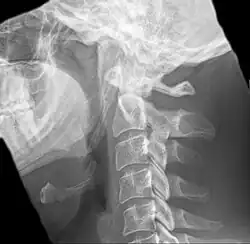

Radiograph, lateral view showing elongated stylohyoid process and stylohyoid ligament ossification -

Radiograph, lateral view showing joint-like formation in ossified stylohyoid ligament -

Diagnosis is suspected when a patient presents with the symptoms of the classic form of "Eagle syndrome" e.g. unilateral neck pain, sore throat or tinnitus. Sometimes the tip of the styloid process is palpable in the back of the throat. The diagnosis of the vascular type is more difficult and requires an expert opinion. One should have a high level of suspicion when neurological symptoms occur upon head rotation. Symptoms tend to be worsened on bimanual palpation of the styloid through the tonsillar bed. They may be relieved by infiltration of lidocaine into the tonsillar bed. Because of the proximity of several large vascular structures in this area this procedure should not be considered to be risk free.

Imaging is important and is diagnostic. Visualizing the styloid process on a CT scan with 3D reconstruction is the suggested imaging technique.[13] The enlarged styloid may be visible on an orthopantogram or a lateral soft tissue X ray of the neck.